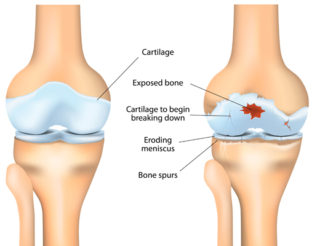

To understand how RA affects your body, it’s helpful to know a little about your joints.

Joints are places where bones meet. Bones, muscles, ligaments and tendons work together so you can twist, bend and move about.

The ends of your bones are covered in a thin layer of cartilage. It acts like a slippery cushion absorbing shock and helping your joint move smoothly.

The joint is wrapped inside a tough capsule filled with synovial fluid. This fluid lubricates and nourishes the cartilage and other structures in the joint.

When you have RA, and the immune system targets your joints, it causes a build-up of synovial fluid and inflammation of the tissues that line the joint (synovial membrane). This causes pain, heat and swelling.

Cartilage becomes brittle and breaks down. Because the cartilage no longer has a smooth surface, the joint becomes stiff and painful.

Ligaments, tendons and muscles surrounding the joint can also be affected, causing joints to become unstable.